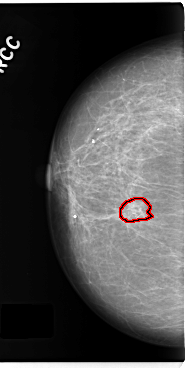

C_0285_1.RIGHT_MLO

C_0285_1.RIGHT_CC

RIGHT_CC LINES 4776 PIXELS_PER_LINE 2400 BITS_PER_PIXEL 12 RESOLUTION 50 OVERLAY

FILE: C_0285_1.RIGHT_CC.OVERLAY

TOTAL_ABNORMALITIES 1

ABNORMALITY 1

LESION_TYPE CALCIFICATION TYPE FINE_LINEAR_BRANCHING DISTRIBUTION CLUSTERED

ASSESSMENT 4

SUBTLETY 4

PATHOLOGY BENIGN

TOTAL_OUTLINES 1

BOUNDARY